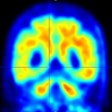

Can PET help redefine 'consciousness' in coma patients?

February 12, 2023